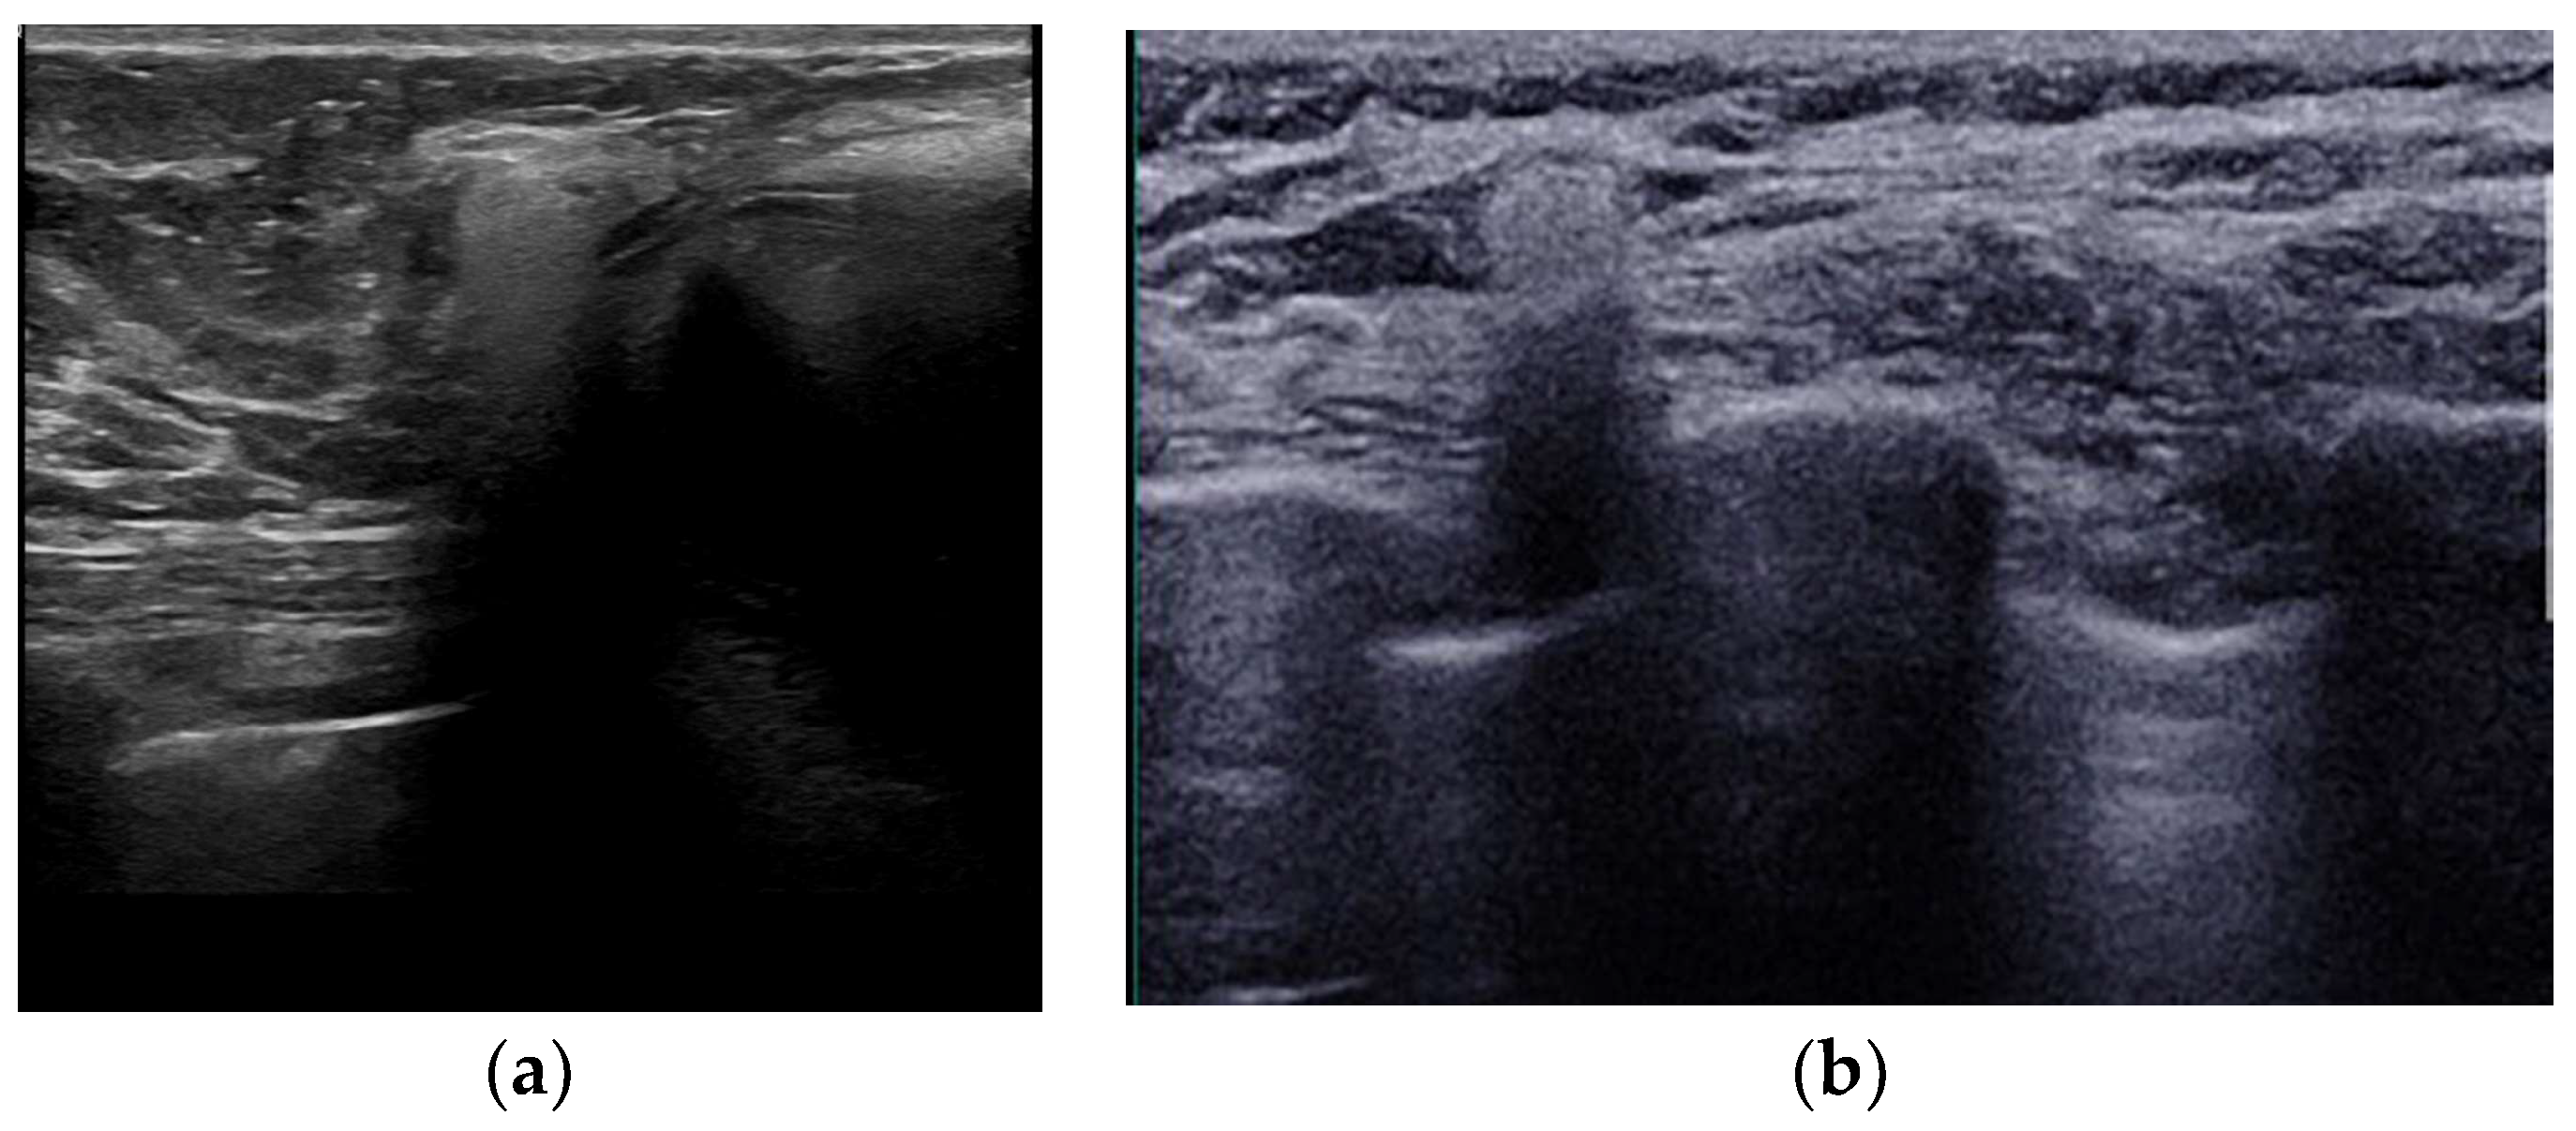

- Salzman, M.J. Silent Rupture of Silicone Gel Breast Implants: High-Resolution Ultrasound Scans and Surveys of 584 Women. Plast. Reconstr. Surg. 2022, 149, 7–14. [Google Scholar] [CrossRef]

- Rochira, D.; Cavalcanti, P.; Ottaviani, A.; Tambasco, D. Longitudinal Ultrasound Study of Breast Implant Rupture Over a Six-Year Interval. Ann. Plast. Surg. 2016, 76, 150–154. [Google Scholar] [CrossRef]